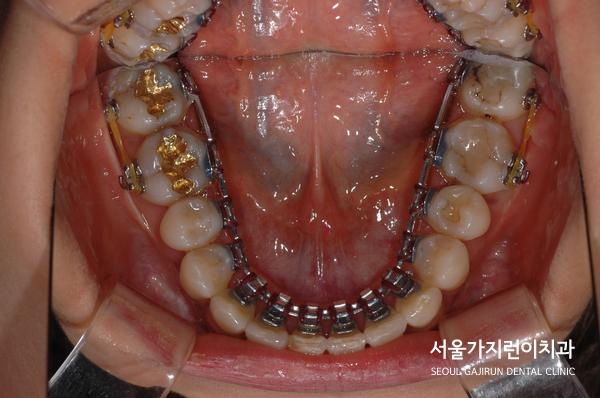

교정으로 할 때 임플란트의 존재와 임플란트 주변의 치아이동에 제한이 있다는 점을 염두하고 치아교정 계획을 수립해 진행하기로 했습니다. 또한 설측교정 방식을 적용해 치료를 진행했는데요. 두 개의 와이어로 설측탄댐교정을 진행해 치아이동에 필요한 힘을 안정적으로 주었습니다. 여기에 잇몸에 미니스크류를 식립해 고정원으로 삼고 이동을 시켰는데요.

환자분의 경우 상악 앞찌가 안쪽으로 기울어진 상태였다가 하악앞니는 덧니 소견도 있었는데요.